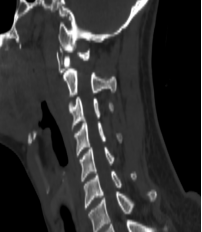

患者杨先生在春节后返苏的高速上不慎发生车祸,事故发生后患者感觉颈部剧烈疼痛,无法活动。当天送至我院后,在急诊拍摄颈椎CT显示:第一颈椎骨折,移位明显。

在仔细研究了患者的片子后,发现寰椎前后弓四处骨折,双侧侧块漂浮,寰齿间隙增大,后弓的骨折块还陷入到椎管内。尽管没有造成颈髓损伤,但稍有移动就可能导致瘫痪甚至死亡,因此姜主任确定该患者的最佳治疗方案为寰枢椎内固定手术。

在麻醉手术科的配合下,有了高精尖的第二代“O”-臂机的辅助,加之姜主任丰富的临床经验,手术非常顺利。第二代“O”-臂机扫描颈椎三维重建显示寰椎移位的骨块复位完成,寰枢椎椎弓根螺钉位置良好。术后,患者颈部疼痛症状明显改善。